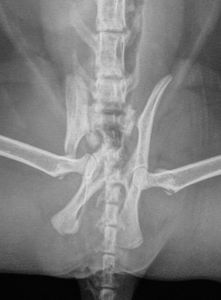

Não tinha noção, mas ao chegar no Vet, ela fez raio x do  quadril, ultrassom e foi quando vimos o quadril dela todo quebrado! 😔

Ela colocou placa e pinos no quadril e ainda tava correndo risco de vir a óbito.